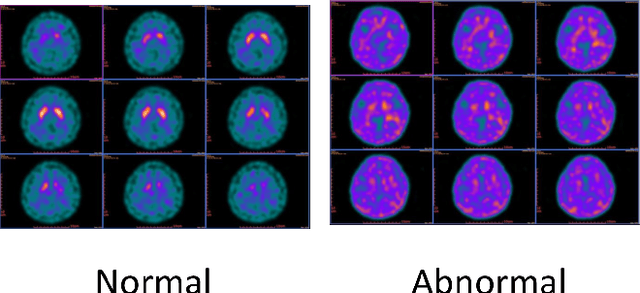

Abstract:Neurodegenerative parkinsonism can be assessed by dopamine transporter single photon emission computed tomography (DaT-SPECT). Although generating images is time consuming, these images can show interobserver variability and they have been visually interpreted by nuclear medicine physicians to date. Accordingly, this study aims to provide an automatic and robust method based on Diffusion Maps and machine learning classifiers to classify the SPECT images into two types, namely Normal and Abnormal DaT-SPECT image groups. In the proposed method, the 3D images of N patients are mapped to an N by N pairwise distance matrix and are visualized in Diffusion Maps coordinates. The images of the training set are embedded into a low-dimensional space by using diffusion maps. Moreover, we use Nystr\"om's out-of-sample extension, which embeds new sample points as the testing set in the reduced space. Testing samples in the embedded space are then classified into two types through the ensemble classifier with Linear Discriminant Analysis (LDA) and voting procedure through twenty-five-fold cross-validation results. The feasibility of the method is demonstrated via Parkinsonism Progression Markers Initiative (PPMI) dataset of 1097 subjects and a clinical cohort from Kaohsiung Chang Gung Memorial Hospital (KCGMH-TW) of 630 patients. We compare performances using Diffusion Maps with those of three alternative manifold methods for dimension reduction, namely Locally Linear Embedding (LLE), Isomorphic Mapping Algorithm (Isomap), and Kernel Principal Component Analysis (Kernel PCA). We also compare results using 2D and 3D CNN methods. The diffusion maps method has an average accuracy of 98% for the PPMI and 90% for the KCGMH-TW dataset with twenty-five fold cross-validation results. It outperforms the other three methods concerning the overall accuracy and the robustness in the training and testing samples.